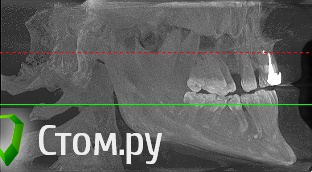

sergey765 Опубликовано 11 июня, 2014 Автор Поделиться Опубликовано 11 июня, 2014 посмотрите пожалуйста КТ. Ссылка на комментарий

sergey765 Опубликовано 11 июня, 2014 Автор Поделиться Опубликовано 11 июня, 2014 могу вам ещё снимков выложить.их довига. беспокаят меня боли после удаления .прошло 5 недель. снимки девушка лет 20 эти смотрела. сказала что у меня там инфекции дофига. типа давай я тебя на понедельник к хирургу запишу. он ранку вскроет. прочистит Ссылка на комментарий

Bier Опубликовано 11 июня, 2014 Поделиться Опубликовано 11 июня, 2014 это все не информативные кадры, в прикрепленных темах есть инструкция, выкладывайте КТ целиком, наш рентгенолог скачает и выложит срезы. 3 Ссылка на комментарий

sergey765 Опубликовано 12 июня, 2014 Автор Поделиться Опубликовано 12 июня, 2014 хорошо сейчас скидываю весь диск в рар архиве в файлообменник. люди добрые пожалуйста скачайте посмотрите. умоляю на коленях. ситуация у меня крайне серьезная. мне нужно чтобы хороший хирург посмотрел. в долгу не останусь. и если что у меня сильно там серьезное приеду к вам в клинику в москву/питер. а там что-то полюбас будет..... вчера когда делал КТ в частной клинике девочка (лет 20) смотрела, нифига вроде не поняла, сказала только у меня там инфекции полно (где там я не понял) и лунка удаленного зуба не заживает типа надо хирургу показать он вскроет прочистит т.е возможно когда мне зуб удаляли не прочистили там ничего... сейчас меня беспокоят боли в районе подбородка. самочувствие моё плохое. с кровати почти не встаю. все написано в начале данной темы.умоляю скачайте посмотрите. томограмма сделана программой iCATVision Ссылка на комментарий

sergey765 Опубликовано 12 июня, 2014 Автор Поделиться Опубликовано 12 июня, 2014 (изменено) ещё хочу добавить. когда у меня удаляли 5 недель назад мой зуб. из лунки выскочил какой-то кусок черного мяса размером почти с горошину. это не кровяной сгусток а именно кусок застывшиго черного мяса. крови почти не было. так во этот кусок мяса залез обратно в десну-челюсть только дня через 4. и видна в лунке была только челюсть желтого цвета и посередине дырка из кости куда этот кусок мяса залез. потом я пришел к врачу который удалял она мне на кость положила лекарство желтого цвета которое тупо застыло и не растворялось. стало как камень. от запаха этого лекарства я реально чуть не сдох. так было ещё дней 5. потом лунка затянулась но кусок желтой кости торчит досихпор. еще при удалении пол левой челюсти побелело. образовался какой-то белый налет на левой половине верхней и нижней десне. через 2-3 дня после удаления я провел пальцем по деснам и этот налет с десны снялся но остался белый комок на пальце которым я проводил по десне... еще у меня постоянно уже года 2 наверно из левого глаза идет временами гной... посмотрите на снимке там даже с левой стороны челюсти (правой снимка) есть какое-то черное пятно. Изменено 12 июня, 2014 пользователем sergey765 Ссылка на комментарий

sergey765 Опубликовано 12 июня, 2014 Автор Поделиться Опубликовано 12 июня, 2014 (изменено) и ещё. удаление было левая сторона нижней челюсти 3-й зуб... 2-й весь страшный вот в нём дофига инфекции. из-под десны там камень или гной идет фиг его знает. а в самом зубе какая-то белая фигня. ну его сказали можно типа вылечить. сейчас короче загружаю файл КТ. размер 310мб Изменено 12 июня, 2014 пользователем sergey765 Ссылка на комментарий